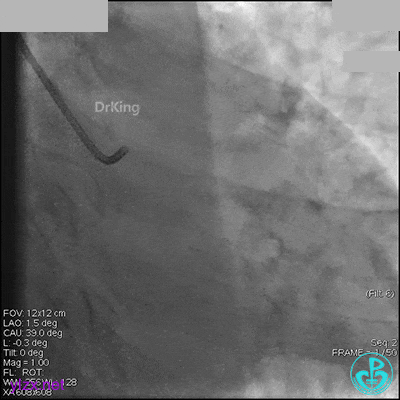

AL 1.0指引导管到位,简单短时尝试导丝不能顺利通过前降支或回旋支病变。改变策略处理右冠脉病变,计划植入2枚支架。AL指引导管到位,Sion blue导丝到达右冠脉远端。导丝通过后1.5mm及2.5mm球囊14~16atm充分扩张中段病变。

右冠脉中段充分扩张后欲植入3.5×38mm支架时,支架难以通过中远段扭曲处,且指引导管、导丝弹出飞扬。反复尝试导丝重新到达右冠脉远端时通过不顺利,局部造影剂滞留,远端血流接近3级。